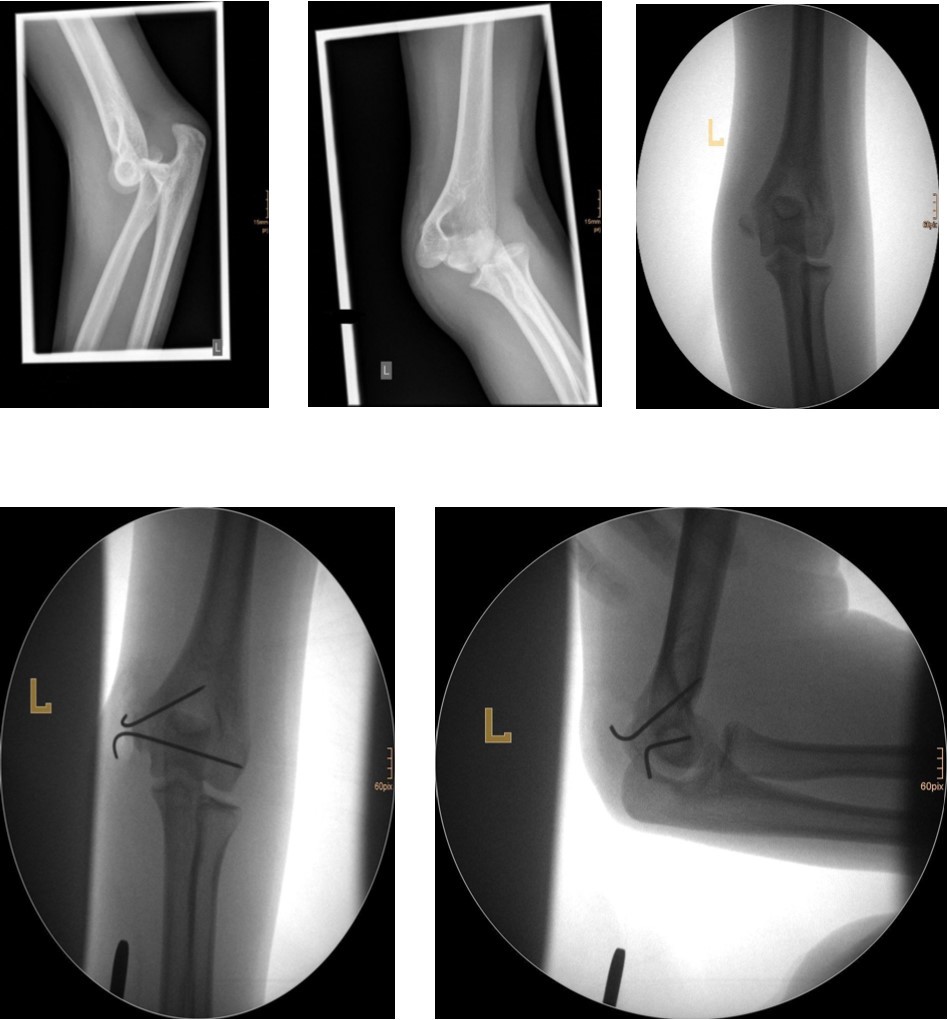

The fracture fragment can be approached by a posteromedial incision that allows good exposure of both the fracture site and the ulnar nerve. Fixation is easily achieved with smooth K-wires or with screws in older adolescents. Two wires are necessary because of the sagittal rotation forces exerted on the fracture fragment by the common flexor muscles. Figure 4 and Figure 5.

Figure 4.14 year old female patient with a elbow dislocation and a dislocated left epicondyle fracture which was treated by open reduction and osteosynthesis with two divergent Kirschner wires (personal collection)

Figure 5.9 year old female patient with a elbow dislocation and a dislocated right medial condyle fracture which was treated by open reduction and osteosynthesis with a screw (personal collection)